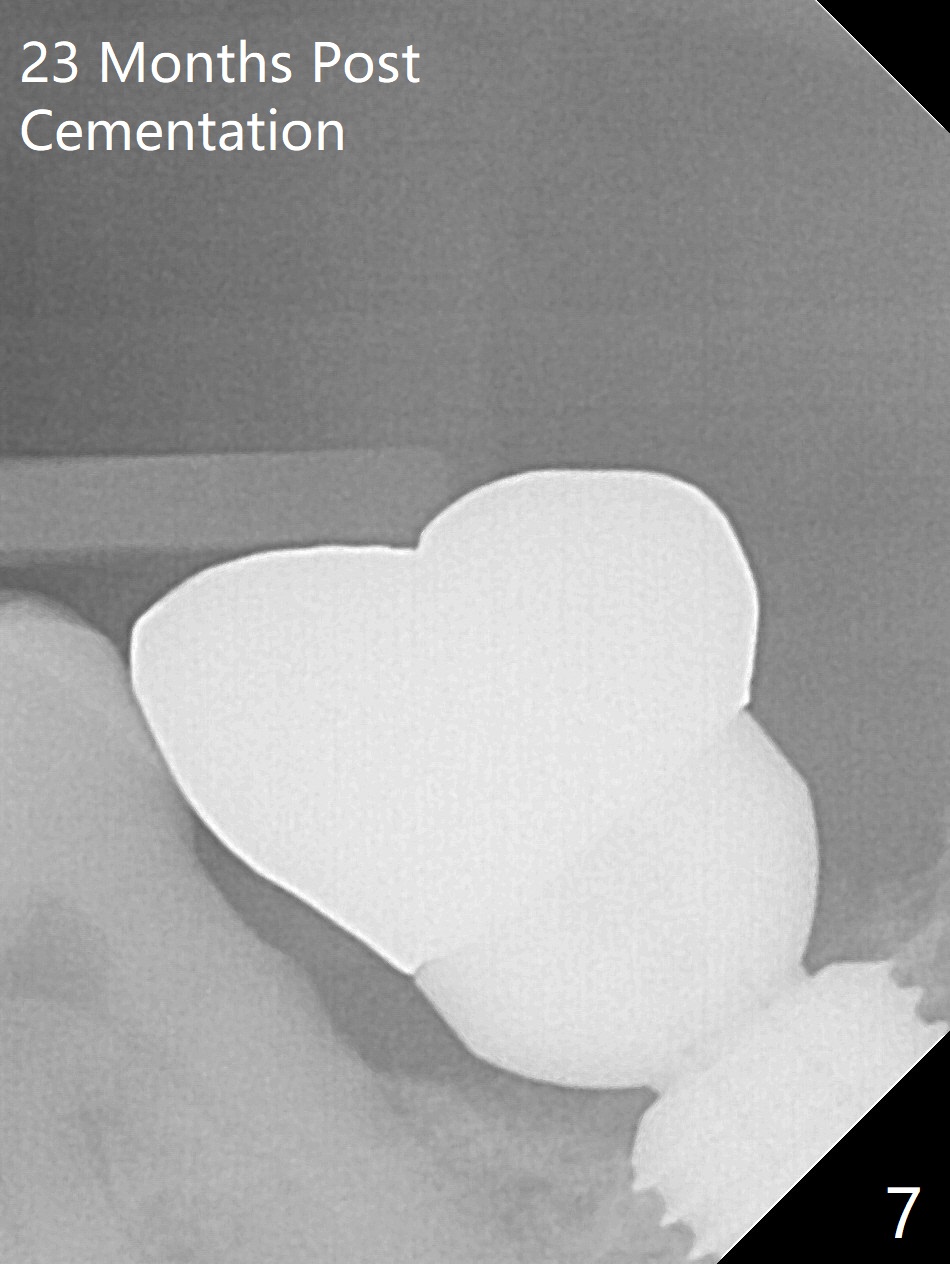

After extraction, curettage and Clindamycine gauzes in the sockets of the tooth #18 for 3 times, a 2 mm pilot drill makes initial osteotomy in the socket from 8 to 14 mm (Fig.1 (gingival level)). It appears that the osteotomy should move distal (Fig.1: red line, Fig.2 (17 mm)). After 5.9x10 mm drill, a 5.9 mm tap is placed (Fig.3). There is 4 mm clearance. Following 6.4x10 mm drill for 2 mm deeper, a 6.4x10 mm implant is placed with 60 Ncm. The implant plateau is level with the lingual crest, while the mesiobuccodistal bone is low. Autogenous bone mixed with Osteogen is placed in the defect area, followed by insertion of a 6.8x4(4) mm abutment (Fig.5). Collagen dressing is placed on the top of the graft. An immediate provisional is fabricated to close the remaining socket. Impression is taken 7 months postop (Fig.6). There seems to be no bone loss 23 months post cementation without opposing teeth (Fig.7) in spite of severe periodontitis at #19 (Fig.8 (25 months post cementation)). More surprising is the asymptomatic lingual (L) plate perforation, revealed by CT (Fig.9 arrowheads).